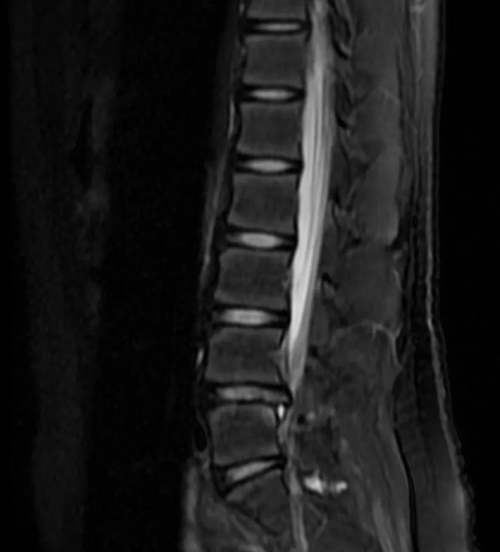

“患兒就診時(shí)已經(jīng)出現(xiàn)了嚴(yán)重的脊柱彎曲保護(hù)體位,并且右側(cè)下肢肌力出現(xiàn)明顯減弱,我們結(jié)合腰部磁共振結(jié)果,發(fā)現(xiàn)患兒腰椎第4-5椎間盤明顯向右后方突出,判斷她患有脊柱外傷引起的腰椎間盤突出癥?!毙汗强贫鹬魅谓榻B說。